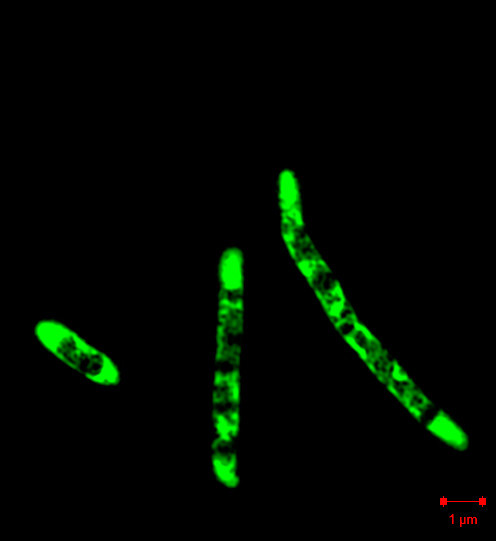

Ved fornyet anamnese fremkom det at pasienten hadde hatt akvarium hjemme i over fem år, og at hun regelmessig matet fiskene, rengjorde akvariet og skiftet vann uten å bruke hansker. Dette ga mistanke om infeksjon med Mycobacterium marinum, en atypisk mykobakterie som kan infisere akvariefisk. Ny biopsi, denne gangen fra kanten av lesjonen, viste hud med granulomatøs betennelse med langerhanske kjempeceller. Dyrking av biopsi på 7H10-medium ved 32 °C viste etter flere uker oppvekst av bakterier. Direkte mikroskopi med auraminfarging viste syrefaste stavbakterier (høyre bilde), som ble identifisert som M. marinum ved 16S rRNA-gensekvensering (1). Polymerasekjedereaksjonstest for M. tuberculosis var negativ.